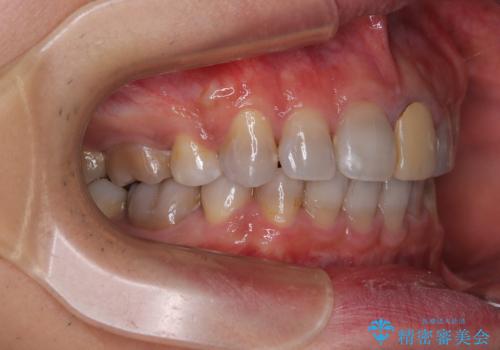

- 飛び出した前歯を気にして来院された患者様です。

口元を引っ込めるために上下左右の第一小臼歯4本を抜歯することとしました。

特徴的な歯の色が気になっているとのことで、今後セラミッククラウンによる審美歯科治療を検討されているとのことで、矯正治療の後戻りが落ち着いたタイミングで治療を進めていく予定です。